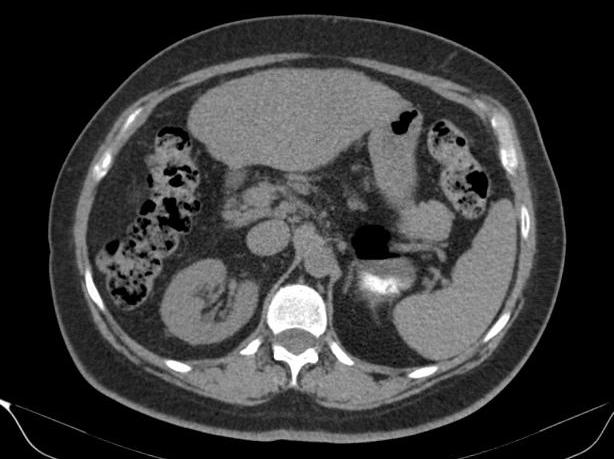

Túi thừa dạ dày - Ảnh 2

Túi thừa dạ dày

» Thông tin: Nữ giới – 54 tuổi.

» Lâm sàng: Kiểm tra sức khỏe.